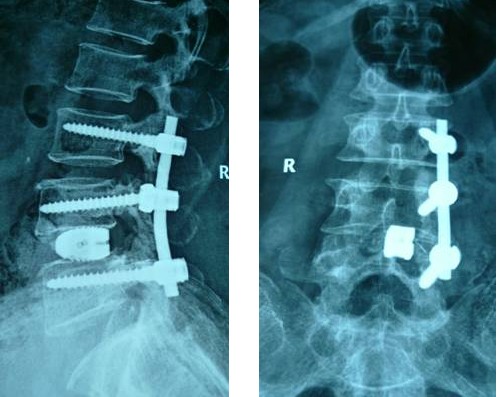

病例匯報(bào)2老年女性患者,因“反復(fù)腰腿痛10年、加重伴左下肢麻痛3年”之主訴入院,術(shù)前間斷性跛行,左下肢肌力3+級(jí),淺感覺減退。術(shù)后腰腿疼緩解,肌力及感覺恢復(fù)正常。(1、圖2)

術(shù)后腰椎X線提示單側(cè)釘棒系統(tǒng)固定穩(wěn)妥,椎間隙高度恢復(fù)正常,融合良好。(圖2